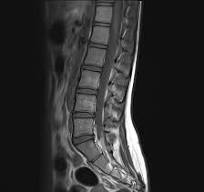

An MRI is good at showing structural problems. Torn rotator cuffs. Herniated discs. Advanced arthritis. But most chronic pain patients do not have something that obvious.Instead, the problem often comes down to adhesion and nerve entrapment.Adhesion is like glue that builds up between muscles, tendons, and nerves. It forms when your body heals from injury or breaks down from repetitive use. These tissues are supposed to slide smoothly. When they get glued together you lose movement. When nerves are trapped they lose blood flow and start to send pain, weakness, or tingling.Adhesion is the most common and most overlooked cause of chronic pain in adults. And it never shows up on an MRI.That is why so many people bounce from provider to provider with clean scans but no relief.